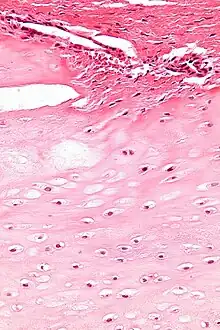

| Micrograph of an enchondroma. H&E stain. |

Enchondroma is a type of benign bone tumor that originates from cartilage. The exact etiology of it is not known. An enchondroma most often affects the cartilage that lines the inside of the bones. The bones most often involved with this benign tumor are the miniature long bones of the hands and feet. It may, however, also involve other bones such as the femur, humerus, or tibia. While it may affect an individual at any age, it is most common in adulthood. The occurrence between males and females is equal. It is not very likely that the enchondroma will grow back in the same spot; the rate is less than ten percent.